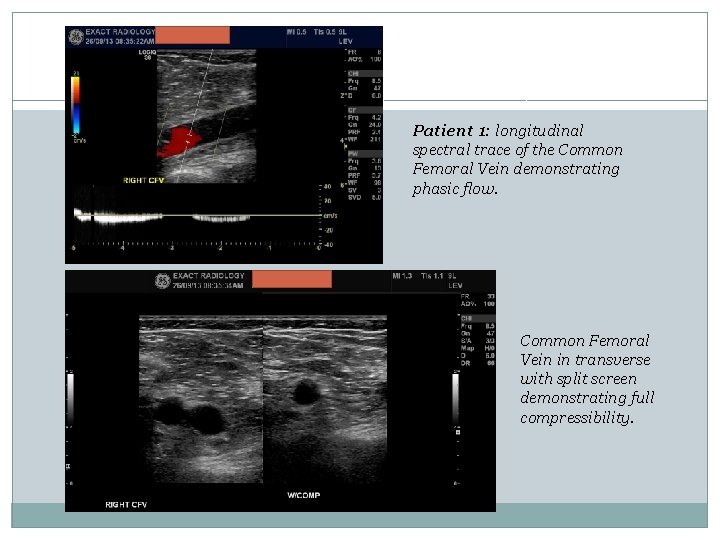

Patient 1: longitudinal spectral trace of the Common Femoral Vein demonstrating phasic flow. Common Femoral Vein in transverse with split screen demonstrating full compressibility.